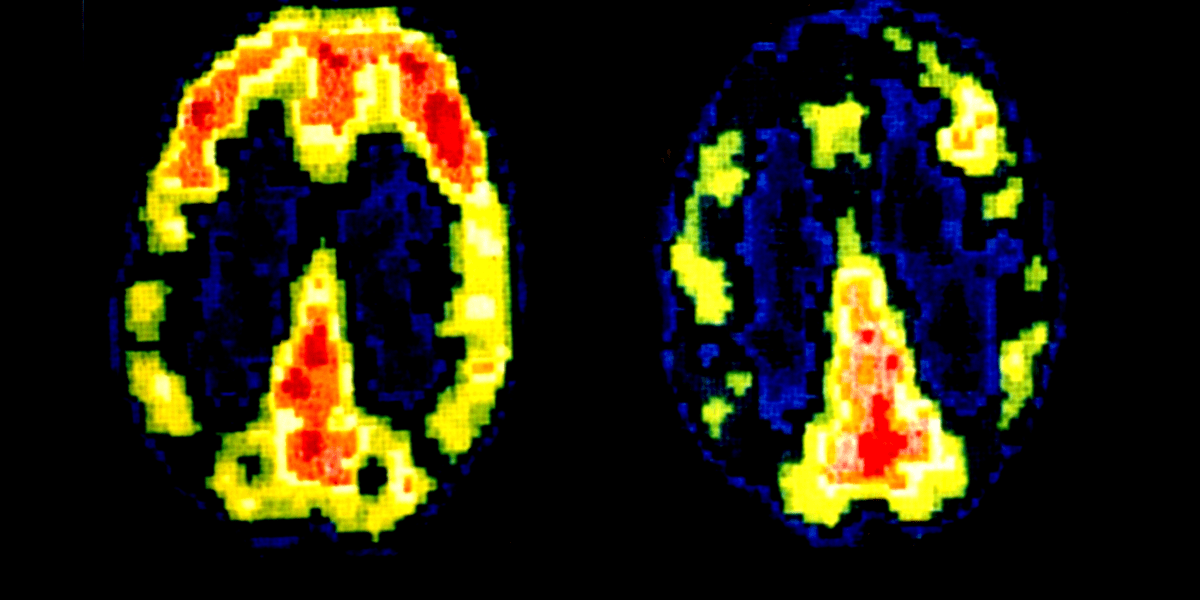

Wie das Gehirn eines Mörders aussieht